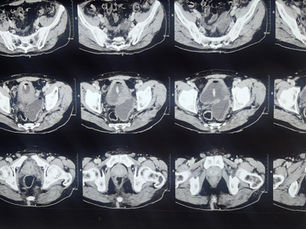

PLND in RP: Status in PSMA PET era?